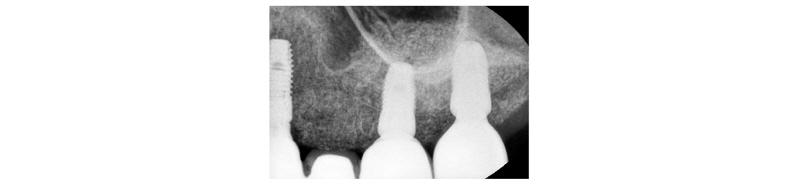

Fig. 32. Periapical x-ray view. Final prosthesis. |

Dong- Wook Chang : The Application of Ridge Splitting Procedure in Severely Atrophied Maxillary Alveolar Ridge: Case Reports. Implantology 2017 |